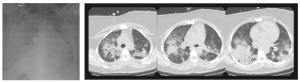

Figura 1: Radiografía de tórax (izquierda) y tomografía computada (derecha, a nivel de tercio superior, medio e inferior) de una mujer de 33 años, que presentó una aspiración pulmonar de contenido gástrico durante la extubación al finalizar una cirugía ginecológica de urgencia. La radiografía de tórax muestra infiltrado pulmonares bilaterales, difusos, y una silueta cardíaca de tamaño normal. La tomografía computada muestra un patrón heterogéneo, con áreas normales y zonas condensadas, que predominan en las regiones dependientes o dorsales del pulmón.

Con el advenimiento de la tomografía computarizada en clínica, Gattinoni y cols. analizaron cuantitativamente los pulmones de pacientes con SDRA, encontrando que el tejido con aireación normal era de 200 a 500 gramos, vale decir, el tejido aireado de un niño de 5 a 6 años [3]. Morfológicamente, el compromiso pulmonar era muy heterogéneo y el tejido con aireación normal estaba disminuído (Figura 1). En consecuencia, en el SDRA se está frente a un pulmón fisiológicamente pequeño, y no rígido como se pensaba, con una menor superficie disponible para el intercambio gaseoso. Así, el uso de volúmenes corrientes (Vt) suprafisiológicos en un paciente con un baby lung es capaz de sobredistender y generar gran tensión (stress) y elongación (strain) del parénquima pulmonar, siendo éste el principal mecanismo causante del daño inducido por la ventilación mecánica.